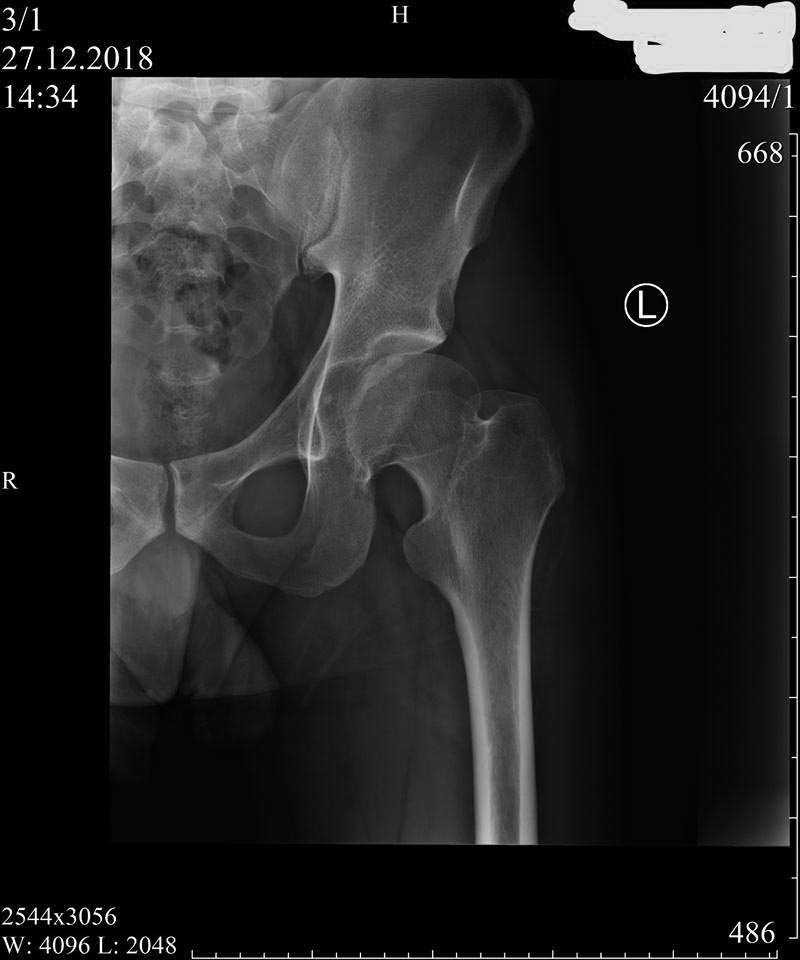

Диагностика дисплазии и импинжмента не такая сложная, на основании обычных стандартных исследовании. Прямой таз, прямой снимок каждого сустава и боковой, иногда требуется снимки в ротации: внутренняя и наружная, в аддукции и абдукции!

На представленном снимке (frog lateral) хорошо можно увидеть шейку и головку, но для данной патологии требуется false profile view! Для удобства приложил некоторые укладки: false profile и снимок с нормальными параметрами сустава (синими указаны центр край угол). Здесь имеется измененная и деформированная диспластическая форма головки, где огромный размер, выходя за пределы вертлужной впадины, создает иллюзию подвывиха. Очень узкая нагрузочная площадь и почти негативный (center-edge angle of Wiberg), потому что вертикаль (зеленая) от центра головки проходит с латеральной стороны. Контур передней стенки (синий) показывает что покрывает головку мало, а задняя стенка (красная) больших размеров доказывает что сустав развернут кпереди. Возможно за счет укладки, на рентгене слева шейка вроде короткая.

В данном случае имеется возможность сохранить сустав, рекомендуется остеотомия таза, которая увеличит нагружаемую поверхность и улучшит переднее покрытие. Тройная остеотомия имеет свои отрицательные стороны, например, из-за вовлечения задней колонны затягивается восстановление и бывают проблемы в акушерской практике. PAO (периацетабулярная остеотомия) таза позволяет исправить все деформации через один передний доступ.